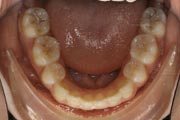

Crowding

After